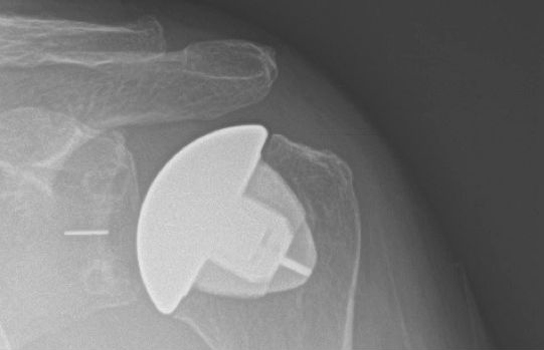

Proximal humerus fractures can involve four sections of the proximal humerus – the shaft, the ball, the lesser tuberosity, and greater tuberosity. Treatment options include non-operative treatment, surgical fixation, and replacement. The vast majority can be successfully treated without surgery. Depending on age, fragment displacement and angulation, some patients have better outcomes with surgical repair or replacement.

Shoulder radiographs demonstrating a complex proximal humerus fracture on the left, treated with a reverse shoulder arthroplasty on the right.